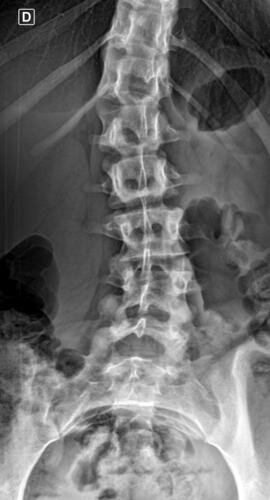

A Vá tem 13 anos e precisa urgentemente realizar uma cirurgia na coluna.Valentina foi surpreendida com o diagnóstico de escoliose hepática grave com 67 graus de desvio (desvio longitudinal da coluna), e precisa realizar com urgência a cirurgia corretiva, os exames foram realizados em Porto Alegre, mas a cirurgia está marcada para dia 13/07 em São Paulo devido a gravidade do caso, para isso a família terá que ficar residindo próximo ao hospital em São Paulo por no mínimo 30 dias para uma plena recuperação. Sabemos bem que qualquer procedimento cirúrgico é delicado, na coluna então nem se fala.Após o diagnóstico e o prognostico dessa doença a família se desfez de alguns bens (carro e moto) para cumprir os prazos dos exames e consultas, necessitando agora arrecadar o valor para a estadia da pequena Valentina e seu pós operatório (medicação, consultas e fisioterapia).

Em anexo os exames (laudo e imagens) para expressas a gravidade do caso.